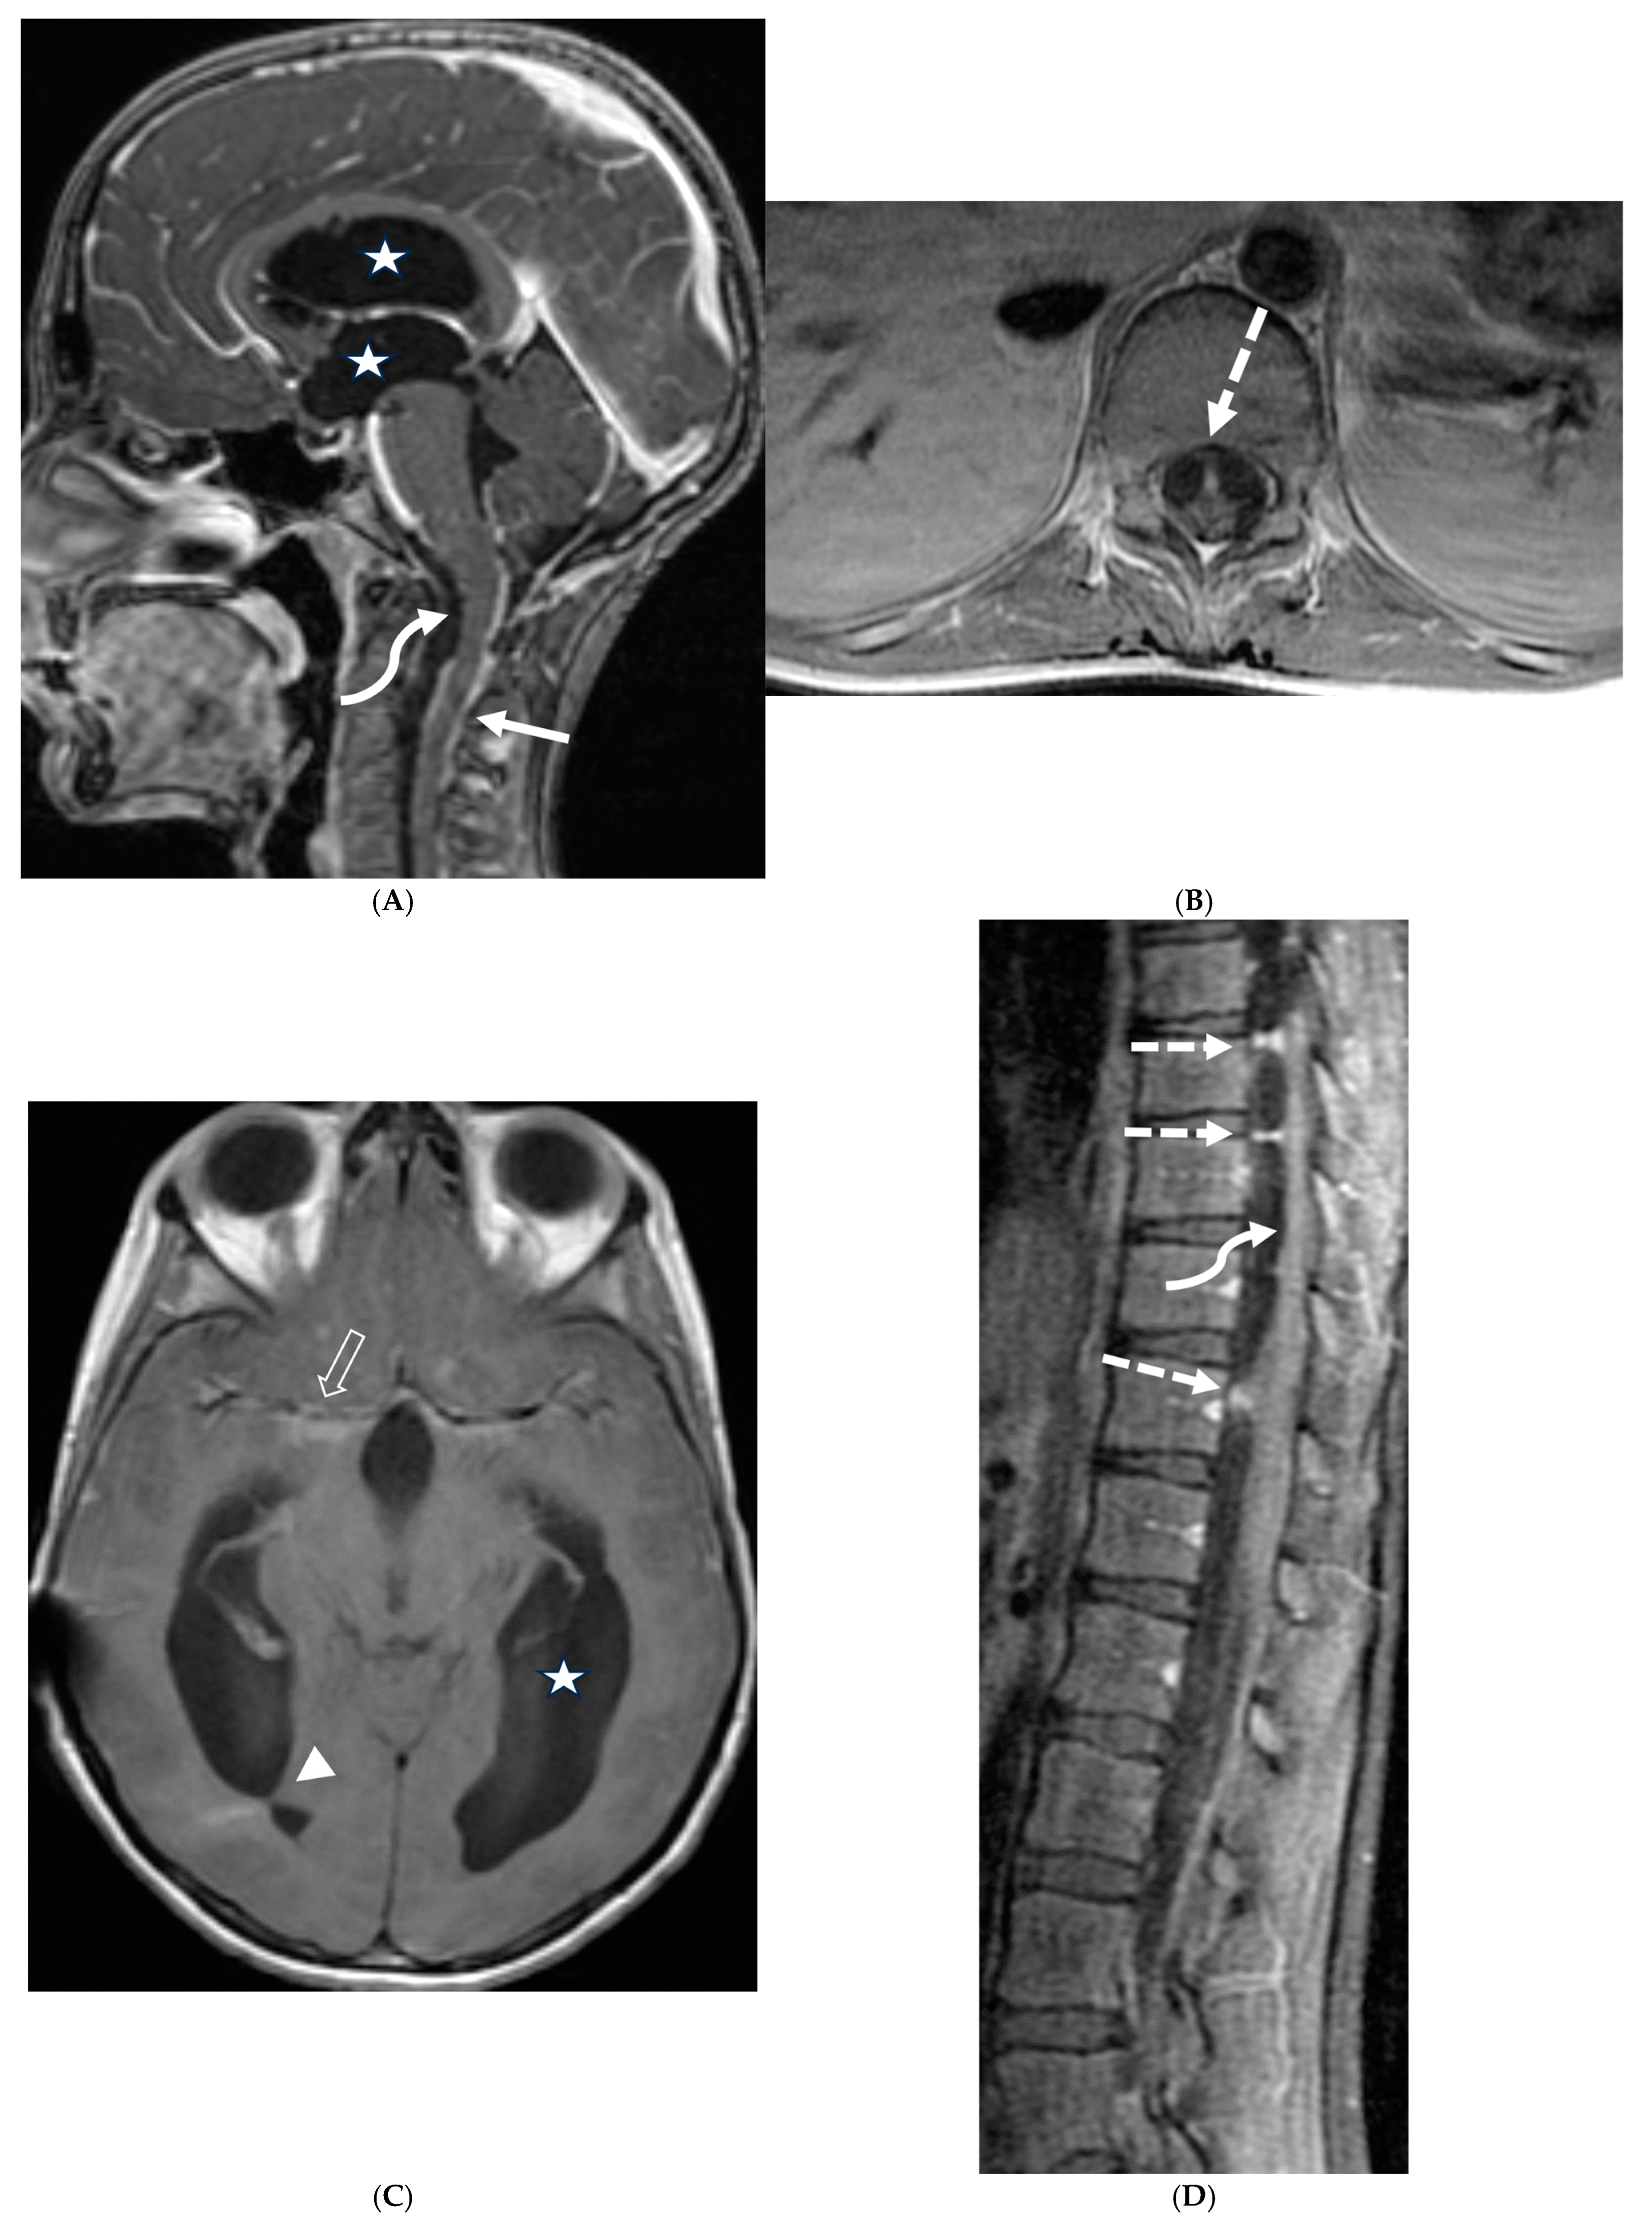

3.8. Intracranial Hypotension (IH)

Intracranial hypotension in children is frequently secondary to iatrogenic causes including lumbar punctures, craniospinal surgeries and ventricular shunt drain pressure changes [64]. Spontaneous causes are commonly connective tissue disorders such as Marfans and Ehler Danlos syndromes. Dural tears and meningeal diverticula have been demonstrated in these cases [65]. Beyond headaches, IH can manifest with nausea, vomiting, light sensitivity (photophobia), and stiff neck [66].

MRI features of IH can be explained by the Monroe-Kellie doctrine, which states that the intracerebral volume including blood, CSF and brain parenchyma remain the same. Thus, a decrease in CSF volume promotes dilatation and rounding of the venous sinuses, subdural fluid collections along with dural (pachymeningeal) enhancement which occurs due to vascular engorgement and transudation of fluid into it [67]. Hyperemia of the pituitary gland occurs which may mimic hyperplasia or pituitary tumor. Brainstem slumping or downward displacement of the brainstem, defined as red nuclei below the tentorium and low lying third ventricle below the sella, are highly specific indicators of IH, observed in half the cases. A pontomesencephalic angle of less than 50 degrees and mamillo pontine distance of less than 5.5 mm are sensitive and specific parameters to suggest IH [66].

With regard to spine imaging, in addition to the intracranial features of dural enhancement, venous engorgement and subdural collection, unique findings include meningeal diverticula, dural ectasia and C1–C2 sign (Figure 8 and Figure 9). Additionally, a CT myelogram may identify the precise location of the CSF leak which can be sealed off with a blood patch [65,68].

Figure 8.

Sagittal T1 (A), post axial T1 (B,C), axial CT myelogram (D) and technetium 99 m DTPA SPECT-CT (E): 16-year-old with Gorham’s disease. There is cerebellar tonsillar herniation and decrease in prepontine cisterns (white arrows). Significant increase in the size of the venous sinuses (dashed arrow). Diffuse pachymeningeal enhancement is seen (black arrows). Cystic-appearing foci at the skull base are in keeping with lymphangiomatosis with contrast pooling into the lytic lesion (curved arrow). Abnormal radiotracer extravasation in the left clival region correlating with lytic lesion (open arrow). Features are in keeping with intracranial hypotension secondary to CSF leak.

Figure 9.

Sagittal T2 FS (A), sagittal (B) and axial (C) T1 post contrast: 3-year-old with neck pain post LP. There is diffuse epidural thickening, with increased T2 signal and enhancement, throughout the cervical, thoracic and lumbar spine (white arrows). Several prominent flow voids are seen within the anterior epidural thickening in the upper cervical region (dashed arrow). There is also increased high T2 signal between the occiput and posterior arch of C1, and between the posterior arch of C1 and spinous process of C2 (curved arrows) in keeping with “C1–C2 sign”. Findings are related to intracranial hypotension post lumbar puncture.